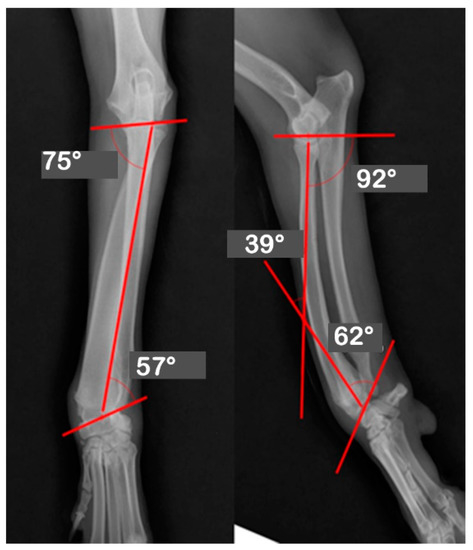

| JOA | Pre-OP | Post-OP | Target | Mean | Reference |

|---|---|---|---|---|---|

| Values | Values | ||||

| aLDRA | 57 | 85 | 85 | 86 | 85~87 |

| aCdPRA | 92 | 87 | 87 | 85 | 84~86 |

| aMPRA | 75 | 84 | 84 | 83 | 82~83 |

| aCdDRA | 62 | 77 | 77 | 77 | 76~78 |

| θ | 38 | 21 | 21 | 27 | 21~32 |